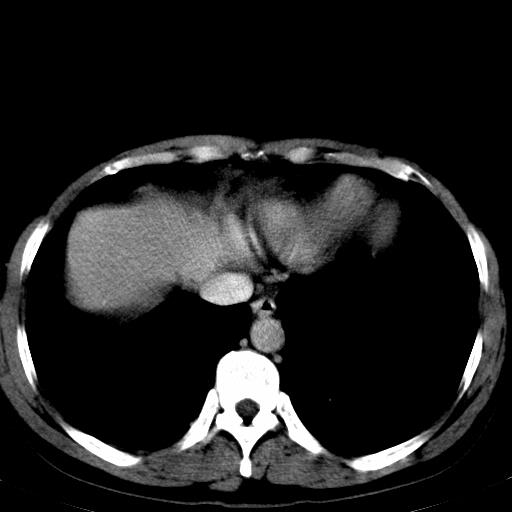

患者上腹部疼痛一月余,伴巩膜黄染;

实事求是的说,强化效果很一般,重点部位应重点观察,但有一点可以明确:肝门部胆管细胞癌。

考虑肝左叶胆管细胞癌侵犯肝门区并肝内胆管及肝总管扩张。

肝左叶肿块清度增强,所在的叶胆管扩张。考虑胆管细胞癌。

考虑肝左叶胆管细胞癌侵犯肝门区并肝内胆管及肝总管扩张、肝门淋巴结肿大。